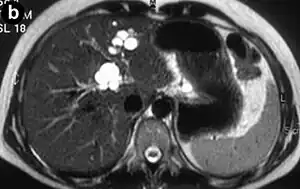

| Turbo spin echo T2-weighted axial MRI of Caroli disease, showing cystic dilatations of bile ducts (shown as white).[1] | |